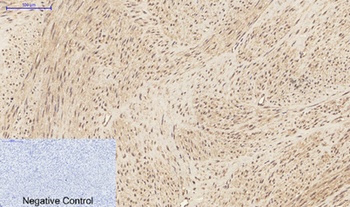

Images & Validation

−Item 1 of 7

| Tested Applications | IHC-P, WB |

| Dilution Range | WB: Western Blot: 1/500 - 1/2000. IHC-p: 1:100-300 ELISA: 1/20000. Not yet tested in other applications. |

IHC-P

Immunohistochemistry Paraffin